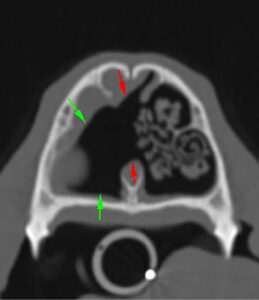

En la TC se apreciaron cambios óseos a nivel de las coanas, compatibles con una malformación congénita asociada o agravada por un posible proceso inflamatorio/infeccioso, que causaba una estenosis marcada de ambas coanas y del aspecto rostral de la nasofaringe (imágenes 1, 2 y 3). Entre los diagnósticos diferenciales de dicha estenosis de tejido blando se incluyeron: un proceso inflamatorio grave o un granuloma infeccioso (principalmente fúngico) sin que se pudiera descartar la presencia de una neoplasia nasofaríngea.

Imágenes 2 y 3. Las flechas rojas indican la lisis completa del tabique nasal en su porción media y la comunicación entre ambas cavidades nasales y las flechas verdes muestran la lisis de cornetes nasales y etmoidales.